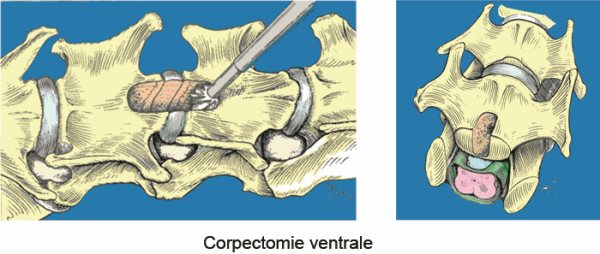

La corpectomie.

Après anesthésie générale, l'animal est disposé en décubitus dorsal.

Le principe est d'aborder le canal vertébral par voie ventrale, en faisant une tranchée au travers des corps vertébraux adjacents pour pouvoir retirer le matériel discal hernié.

L'os est fraisé au moyen d'une fraise neurochirurgicale à très haute vitesse jusqu'au ligament longitudinal dorsal. Le matériel discal peut alors être retiré.

La fenêtre pratiquée dans les corps vertébraux ne doit jamais dépasser la moitié de la longueur et le tiers de la largeur du corps vertébral, au risque d'avoir une luxation du rachis avec télescopage des vertèbres. Chez les animaux de très petite taille, il n'est parfois pas possible de réaliser une corpectomie respectant ces contraintes ; il est alors nécessaire de pratiquer une stabilisation du rachis. Cette stabilisation est réalisée soit au moyen de vis et de ciment chirurgical, soit au moyen de vis et plaques verrouillées en titane.

Stabilisation du rachis cervical par vis verrouillées et plaques intersomatiques en titane.

Après corpectomie, la récupération est normalement très rapide. L'intervention est cependant délicate : des risques de saignements abondants sont possibles en cas de lésions vasculaires.